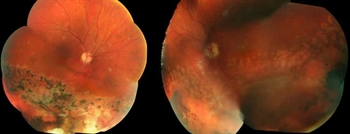

A 45 year-old Caucasian male with no known ocular history presented with slowly progressive, painless bilateral vision over the past 6 years. He states that he has had poor color vision since childhood, but denies any flashes or floaters, trauma, or inciting event. Past medical history is significant only for well-controlled hypertension and hypercholesterolemia. Family history is notable for an older sibling also with poor bilateral vision; remaining family members including parents and children have normal vision.

Best-corrected visual acuity measured 20/60 OD and 20/50-1 OS with minimal myopic correction OU. His pupils, intraocular pressure, motility, and visual fields were within normal limits. Ishihara color plates were 4/17 OD and 3/17 OS. Anterior segment exam was notable for early nuclear sclerosis OU. Dilated funduscopic examination revealed bilateral yellow-white pisciform lesions located within the macula and throughout the periphery (Figure 1).

Spectral-domain optical coherence tomography (OCT) showed bilateral subfoveal atrophy with parafoveal ellipsoid layer irregularities (Figure 2). Fluorescein angiography demonstrated hyperfluorescence corresponding to the areas of the retina lesions along with a dark choroid (Figure 3).